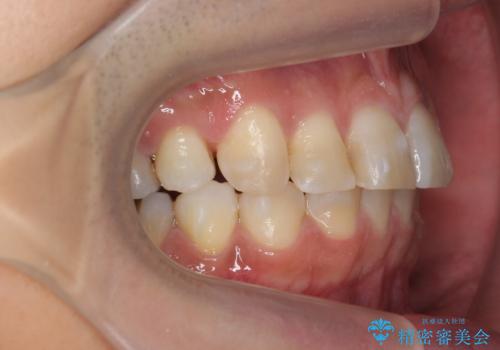

上の前歯が斜めに見えること、犬歯と小臼歯の間の隙間、上下顎前歯のがたつきを治すことをご希望されていました。

矯正期間(マウスピースを装着した期間):3ヶ月2週間(マウスピース14枚、1週間交換)

実際の矯正期間は3ヶ月2週間(マウスピース14枚、1週間交換)と短期間で治療を終えることができました。